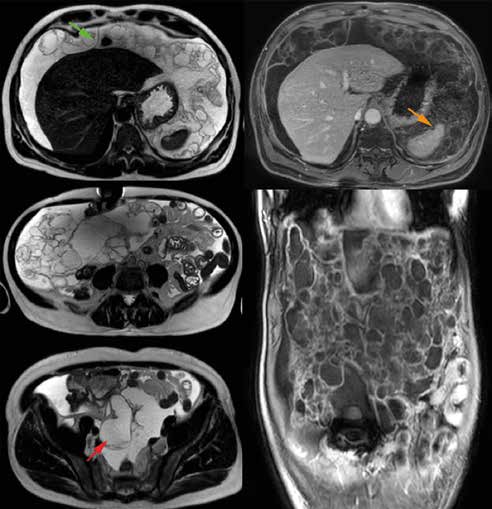

Signes visibles en TDM :

• Encoches sur les organes pleins : scalloping hépatique ou splénique : Flèche orange

• Ascite mucineuse / gélatineuse libre et cloisonnée (prédominant dans les zones de stagnation péritonéales à faible péristaltisme : cul de sac de Douglass, coupoles diaphragmatiques, gouttières pariéto-coliques et grand épiploon)

• Calcifications curvilignes péritonéales : Flèches bleues

• Nodules péritonéaux tissulaires +/- calcifiés dans les formes malignes

• Compartimentation centrale des anses grêles refoulées par la mucine

• Visibilité du ligament suspenseur du foie (foie décollé de la paroi antérieure par prolifération de mucine) : Flèche verte

• Visualisation de la lésion primitive (Dans notre cas : mucocèle appendiculaire : appendice volumineux, hypodense, piriforme avec calcifications pariétales) : Flèches rouges